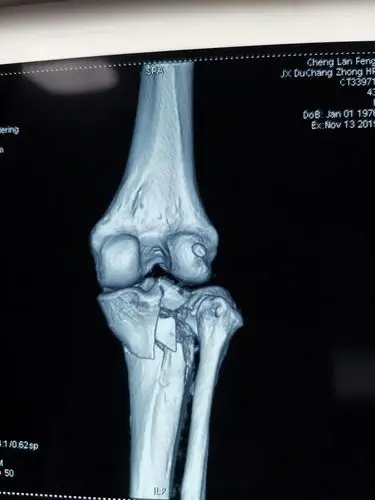

胫骨平台骨折,schatzker 3型,关节镜辅助下复位内固定手术!

ct 三维示:胫骨外侧平台前侧塌陷,有台阶,外侧平台后侧未骨折.